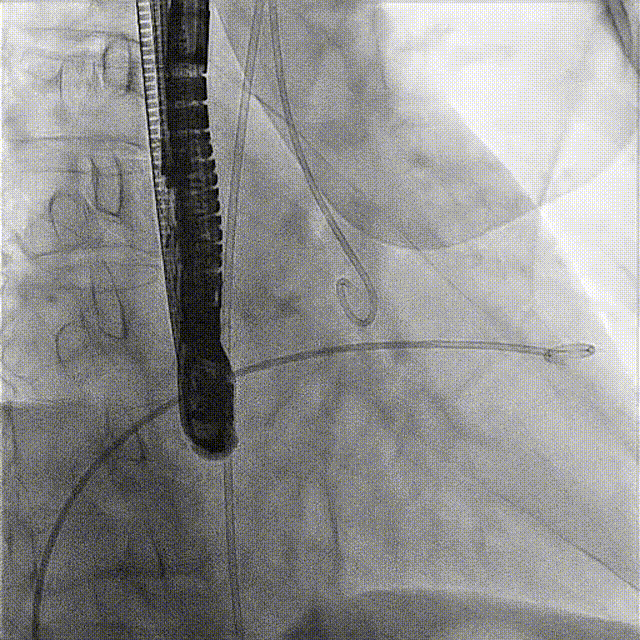

術前DSA

術前經過全面系統的評估后,考慮患者存在高齡、心功能減低、三尖瓣瓣環重度擴張(三尖瓣極重度反流)等高危因素,因此廈心結構心團隊聯合超聲心動、麻醉及護理團隊,制定了詳盡的圍術期治療方案及術中治療難點預案。術中,由王焱院長主刀,在蘇茂龍主任超聲心動團隊的輔助,上海市第一人民醫院陸方林主任的協助下,僅用時30分鐘,即順利完成了三尖瓣原位置換的手術。術中患者血流動力學穩定,術后即刻顯示LuX-Valve Plus瓣膜位置良好,固定穩定,瓣膜功能正常,無瓣周漏。